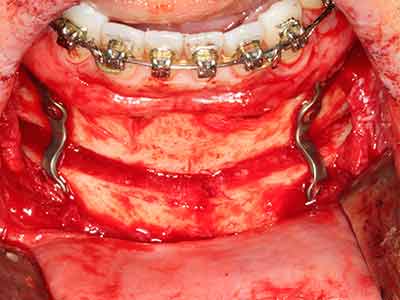

Aplicación: Partición ósea / Cortical Split

El tejido óseo no solo tiene un contenido puramente mineral, sino que también presenta una importante proporción de fibras de colágeno. Esto no solo garantiza una buena resistencia a la presión, sino también una cierta flexibilidad, que puede aprovecharse para la realización de aumentos. En la plastia de expansión clásica a efectos de una partición ósea, la cresta maxilar atrofiada se divide en su eje longitudinal y, tras alcanzar una profundidad de osteotomía suficiente, se extiende con cuidado (fig. 13-16), en un caso ideal sin desperiostizar de forma visible el maxilar (Brugnami, Caiazzo et al. 2014, Stricker, Fleiner et al. 2014). Los sistemas de tornillos y placas con distancia de expansión creciente han demostrado su eficacia para distanciar entre sí las dos tablas óseas por debajo del umbral de rotura. Por regla general, se requieren anchuras de hueso residual de al menos 3 a 4 mm (Chiapasco, Zaniboni et al. 2006) para garantizar una flexibilidad y una cobertura ósea suficientes de los implantes que van a incorporarse. En caso necesario, una osteotomía de descarga vertical unilateral o bilateral puede mejorar la flexibilidad. Como alternativa a la técnica clásica se ha descrito una combinación con otras técnicas de aumento, sobre todo en la parte bucal.

Con el uso de sierras piezoeléctricas la división se efectúa de forma especialmente cuidadosa y sin pérdidas importantes de las dimensiones, por lo que no se han encontrado diferencias significativas entre los implantes realizados en el maxilar dividido y en la cresta alveolar no deficitaria (Chiapasco, Zaniboni et al. 2006, Danza, Guidi et al. 2009). No obstante, precisamente en la partición profunda y limitada de forma local, es preciso asegurarse de que exista una adecuada irrigación por agua para evitar que se produzcan sobrecargas térmicas en las áreas de osteotomía apical.